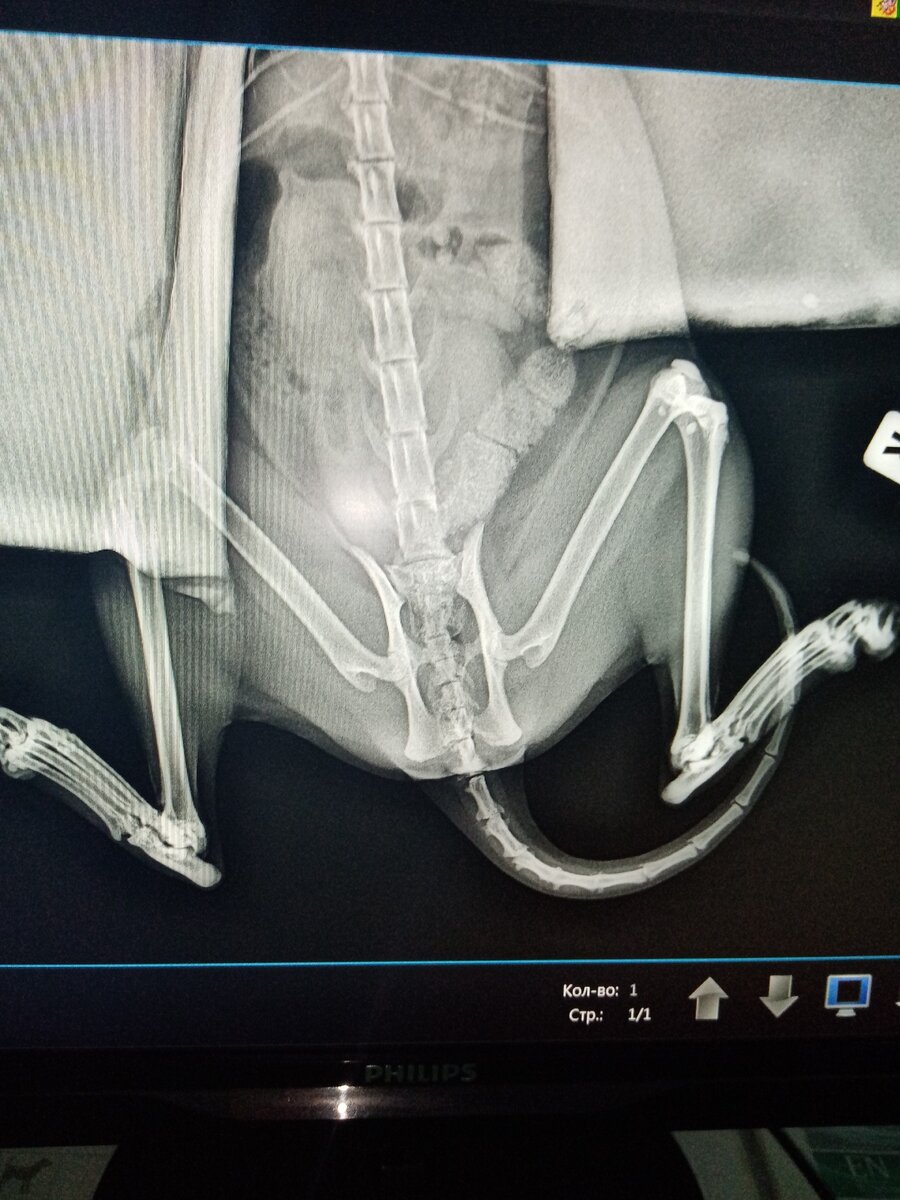

И в самый разгар моей болезни... Когда начался сухой и раздражающий кашель.... Кошка не выдержала.... И прыгнула с третьего этажа с балкона. Конечно, свалилась она по своей неосторожности. Но сколько проблем это принесло.

Рентген был сделан дважды, куча уколов и по сей день они продолжаются. Переломов не обнаружили, но видно проблемы с нервами есть. Не все гладко....